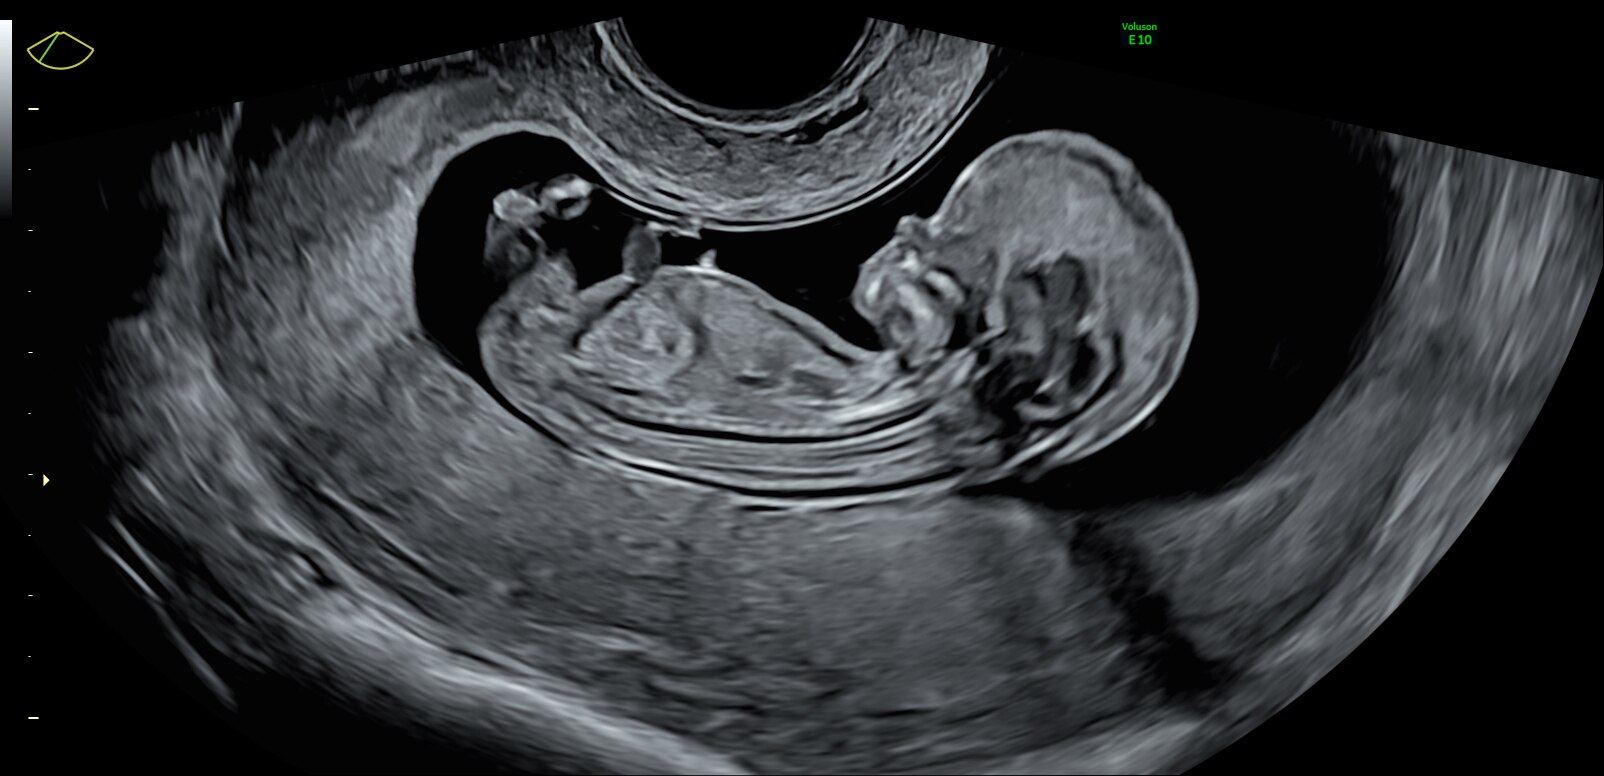

Fetus with HDlive™ generated with SonoRenderlive

13-week fetal profile

HDlive Studio on a 10-week fetus